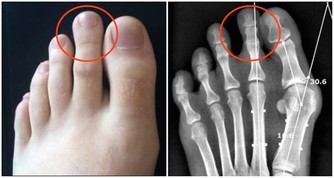

中成藥能引起肝損害的也有很多:壯骨關節丸,多可引起膽汁淤積性肝炎。